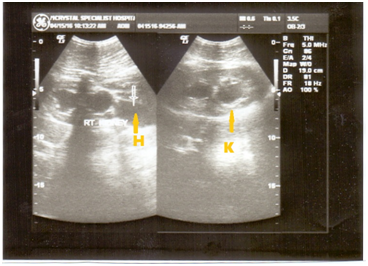

Figure 4 Normal liver (L) and RT kidney (K), the hepato-renal angle (Morissons’ pouch) is within anatomical limits.